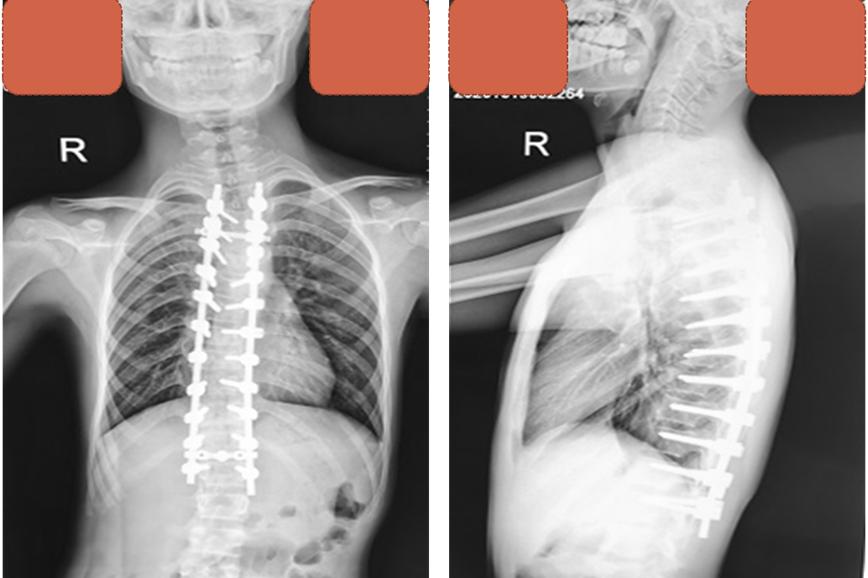

手术中,团队密切配合,采取胸腰椎后入路固定手术,同时在5个节段的脊柱进行截骨,通过直接去旋转技术,将少年高达55度的脊柱侧弯进行全面矫正。保证矫正效果,降低内固定节段过多带来的并发症。“我们还为患儿实行了皮内缝合,伤口无需拆线,孩子身体外观几乎看不出来大手术的痕迹”夏主任说。

术后X线脊柱侧弯基本矫正